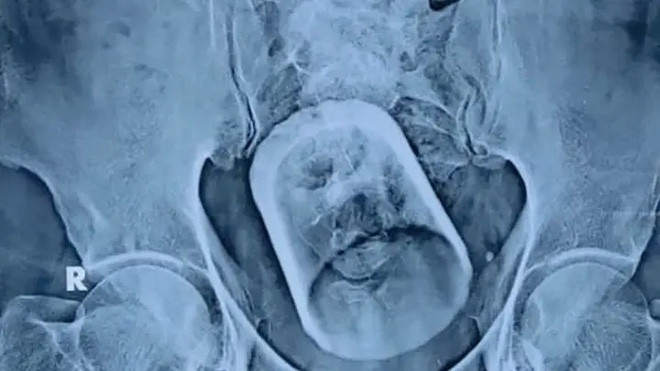

| Hình ảnh siêu âm chiếc cốc trong hậu môn của nam bệnh nhân ở Trung Quốc. |